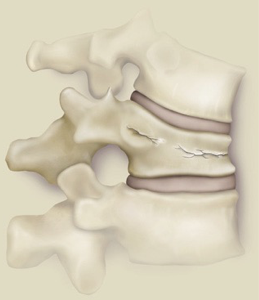

Puedes ver imágenes de una fractura y de la técnica quirúrgica de un caso real del 2015 tras este texto.